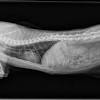

Can Cats Get Lung Cancer / Coping With Cat Cancer Symptoms And Advice Blue Cross - Early identification is key to maximize the likelihood of a positive outcome.. The symptoms of lung cancer may differ depending on where the cancer originated, how aggressive it is, and whether or not the affected cat has suffered from prior lung disease. Cancer can be detected early by observing certain signs and symptoms. Cat cancer is something i was already painfully familiar with. But these facts are no joke. Primary lung cancer, or tumors originating in the lung, are relatively uncommon in dogs (less than 1% of all cancers in dogs), although the number has been increasing.

Early identification is key to maximize the likelihood of a positive outcome. Tumors that cannot be operated on or those. Why have i been given this handout? Cancer in cats is less common than cancer in dogs. The lung is the essential respiration organ whose principal function is to transport oxygen from the atmosphere into the bloodstream, and to release carbon dioxide from the unlike in humans, primary lung cancer is rare in dogs (~1% of all cancers) and even more so in cats. In recent years, a test known as a. The symptoms of lung cancer may differ depending on where the cancer originated, how aggressive it is, and whether or not the affected cat has suffered from prior lung disease. While the causes of cancer in cats are unknown, the feline leukemia virus is suspected to be a prime contributor. Adenocarcinoma is a malignant lung tumor in cats and is usually seen in older animals (more than ten years). Depending on what we come up. Screening is the use of tests or exams to find a disease in people who don't have symptoms. Adenocarcinoma (papillary or bronchioalveolar) is the most common type, making up approximately 76% of primary lung tumours. Adenocarcinoma grows rapidly and metastasizes to distant parts of the body and.

1 in 15 people will be diagnosed with lung cancer. Tumors that cannot be operated on or those. You may have no symptoms at all or you may feel like you have bronchitis or a bad cold that does not get better. It's probably half the rate that we see in dogs. More research is needed to improve lung cancer patient survival, but thanks to the. Lung cancer (adenocarcinoma) in cats lung adenocarcinoma in cats adenocarcinoma is a malignant neoplasm, making up about 75 percent of all primary lung cats (pets) can get fungal lung infections, parasitic nodules, scar tissue or focal pneumonias that can resemble neoplasia. Due to this happening late in the evening i couldn't. We don't see as many. These tumours develop in the lining or inner surface of an organ and. Cancer in cats is less common than cancer in dogs. Can cats get lung cancer? This type of cancer is rare in cats, and accounts for less than 1% of all tumours. The symptoms of lung cancer may differ depending on where the cancer originated, how aggressive it is, and whether or not the affected cat has suffered from prior lung disease.

Due to this happening late in the evening i couldn't. You may have no symptoms at all or you may feel like you have bronchitis or a bad cold that does not get better. Lung cancer is the most common leading cause of death among elderly cats. There's anecdotal evidence that cats have a man claimed that his cat warned him of his lung cancer by dragging his paw down the left side of cats seem to have the potential to sniff out diseases like cancer due to their advanced olfactory. Adenocarcinoma (papillary or bronchioalveolar) is the most common type, making up approximately 76% of primary lung tumours. This type of cancer is rare in cats, and accounts for less than 1% of all tumours. Depending on what we come up. Lung tumors can affect our dogs and cats just like it can us! What are primary lung tumors? In recent years, a test known as a. Learn more about who should get screened and when. Smoking causes most lung cancers, but nonsmokers can also develop lung cancer. Explore the links on this page to learn more about lung cancer treatment, prevention, screening, statistics, research, clinical.